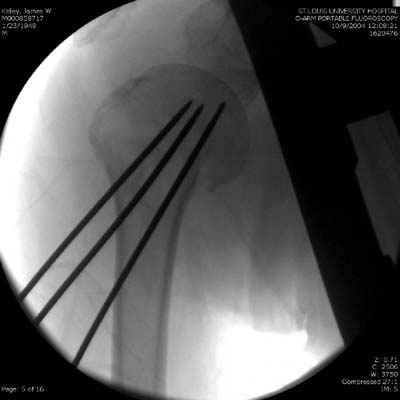

Да. У нас довольно скромный опыт такого остеосинтеза (по 2 случая - плечо и наружная лодыжка), дошли до использования самого простецкого троакара, через который мы сверлим кость и вводим 6 мм стержни, когда накладываем аппарат. Соответственно, в качестве забойника отлично работает любой стержень от аппарата Илизарова. Еще из наших туземных особенностей - страшная любовь к спицевым дистракторам, поэтому делали в нем. Результат у этой дамы неизвестен, т.к. она из области и уехала рожать сразу после остеосинтеза, сейчас прошло больше 5 месяцев...

Что-то, наверно, сделали мы не совсем оптимально, поскольку у Анатолия Федровича и его соратников как-то красивее "раскрываются" спицы в головке плеча - надеюсь, он прокомментирует и подскажет, что надо подправить.

Клинические снимки - 3 недели после операции